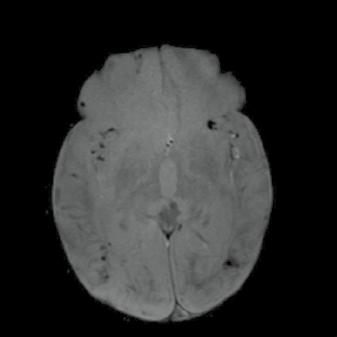

Chlapec, stáří 14 dnů, protrahovaný porod, kříšen, po porodu hypertonický, křeče, poruchy vědomí.

Obr. A3.1–A3.4 „Super scan“ – kombinace periferního a centrálního typu postižení, s krvácením. Šipka v obr. A3.1 – centrální léze, šipka v obr. A3.3 – drobná krvácení, šipka v obr. A3.4 – periferní léze A3.1